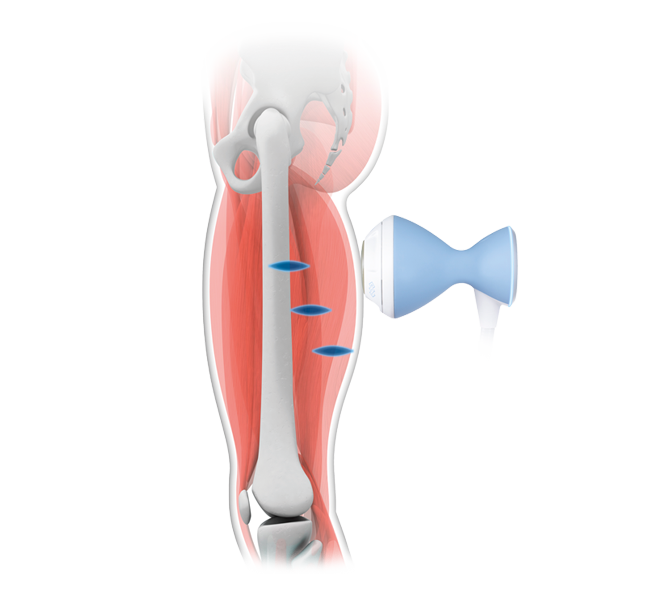

Tendinopathy

Tendinopathy -

The focused shockwave causes deep cell stimulation that releases growth factors responsible for tissue regeneration and the initiation of healing processes in the damaged tissues.

It is a gold standard treatment for deep-lying tendinopathies, calcifications, and delayed bone healing conditions, such as pseudoarthrosis.

The perfect balance between energy flux density and focal zone allows for delivering a high amount of energy to a large area.